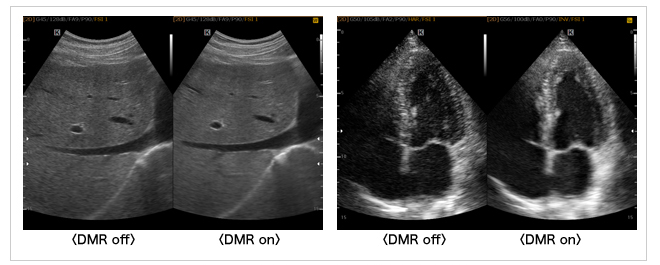

SONIMAGE 613は,DMR USB™*を搭載することが可能です。 DMR USB™は,連続する画像信号を平滑化して滑らかに表示し,信号差がある場合は識別性を向上させる処理を行います(図13)。

図13 視認性の高い画像が得られるDMR USB™